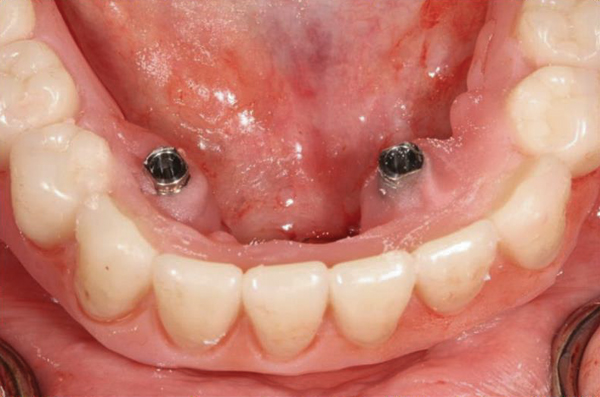

Fig 18. The patient’s intraoral condition.

Figure 18

Dental rehabilitation with the All-on-4 treatment concept is often a life-changing event for edentulous and terminal dentition patients that results in unprecedented quality of life improvements (Figure 17 through Figure 20).